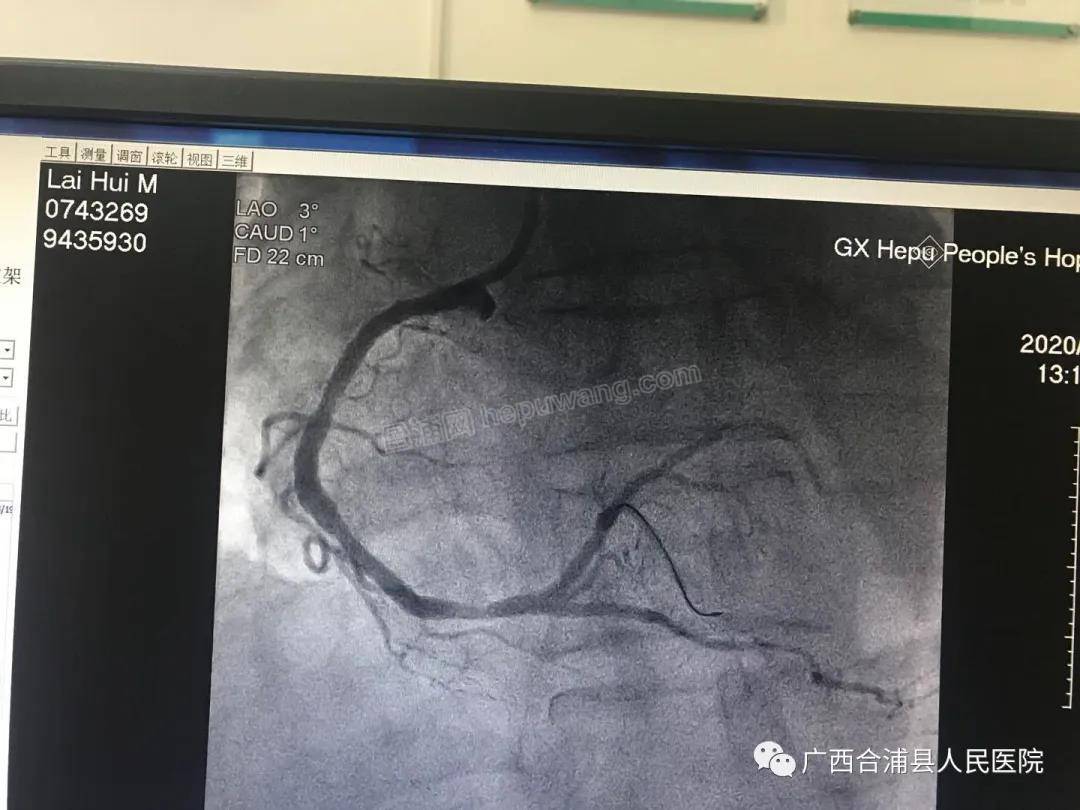

冠脉造影显示为右冠近段完全闭塞,情况非常紧急,必须马上开通闭塞的血管!手术过程惊心动魄,患者病情变化之快始料未及,刚完成冠脉造影,患者的血压骤降至80/50 mmHg,心率45次/分,期间反复出现13次室颤,甚至还出现心脏骤停。“患者出现室颤,神志不清,给予双相波200焦耳非同步电流进行电除颤;立即给予阿托品提高心率,多巴胺、阿拉明升压;患者再发室颤,静推胺碘酮对抗......”心内科主任赖美声组织团队为患者提供高级心血管生命支持, “莫小燕(副主任医师)负责电除颤,黄齐海(主治医师)进行心外按压,袁翠玉(护师)负责气道管理,黄祖霞(护师)负责静脉通道管理......”在团队的密切配合和支持下,廖伟杰及助手邹旭主治医师心无旁骛快速植入2枚支架开通了闭塞血管,患者室颤得以停止,恢复正常心律。13时25分,患者安返病房。